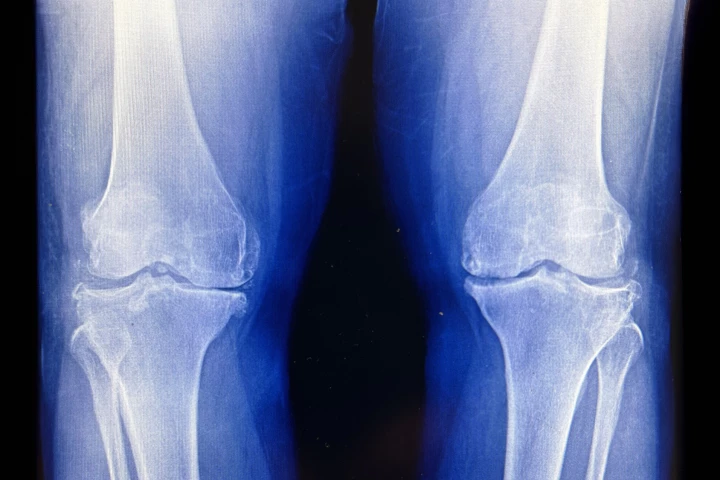

Knee

Knee and things related to the knee joint